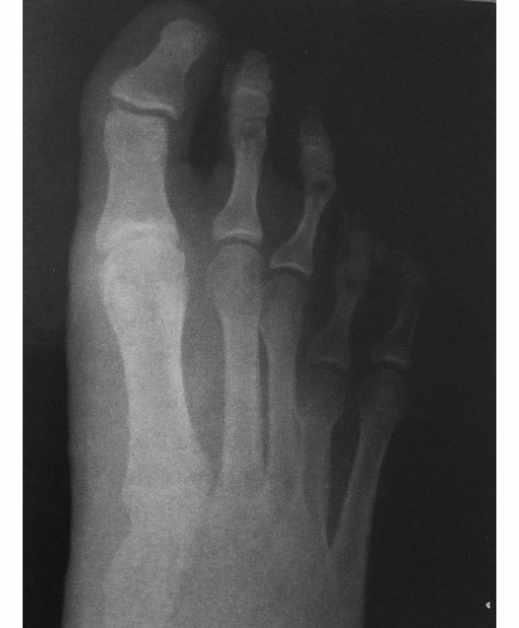

La Braquimetatarsia es un acortamiento anormal de uno o más metatarsianos, causado por un cierre prematuro del cartílago de crecimiento.

El cuarto metatarsiano es el más comúnmente afectado y tiene predominio en las mujeres. En la mayoría de los casos se presenta en ambos pies.

Los pacientes con este acortamiento metatarsal pueden presentar molestias al caminar por mal reparto de cargas dado que el metatarsiano afectado es más corto y puede no ser funcional, pero en la mayoría de los casos acuden a consulta por cuestiones estéticas.

Radiografía de paciente con metatarsalgia previa a someterse a Cirugía